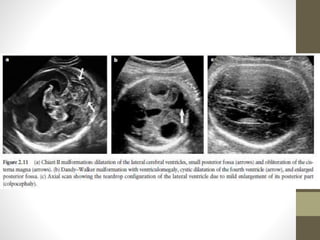

Dandy-Walker

Roof of 4 t Ventricle IS

Undeveloped

โ€ข Cisterna Magna abnormal

โ€ข Enlarged

โ€ข Comms 4th ventricle

โ€ข No roof

โ€ข Post Fossa cyst

โ€ข Tentorium elevated

โ€ข Cerebellum hypoplastic

โ€ข Hydrocephalus

AGENESIS OF CORPUS CALLOSUM

(ACC)

โ€ข The normal development of the corpus callosum begins anterior

(genu) and progresses to posterior (splenium). Agenesis may be

partial (affects dysgenesis posterior aspects) or complete.

โ€ข US Features

โ€ข The corpus callosum is not visible in complete agenesis.

โ€ข โ€ข Colpocephaly

โ€ข โ€ข Lateral ventricles are displaced laterally (parallel lateral ventricles).

โ€ข โ€ข Enlarged 3rd ventricle expands superiorly (high riding third

ventricle).

โ€ข โ€ข Angulated frontal horns (coronal view)( U or VIKING HORN

CONFIGURATION)

โ€ข โ€ข Abnormal (sunburst) gyral pattern in interhemispheric fissure is a

late feature.

โ€ข โ€ข The presence of a cavum septum pellucidum excludes complete

Agenesis